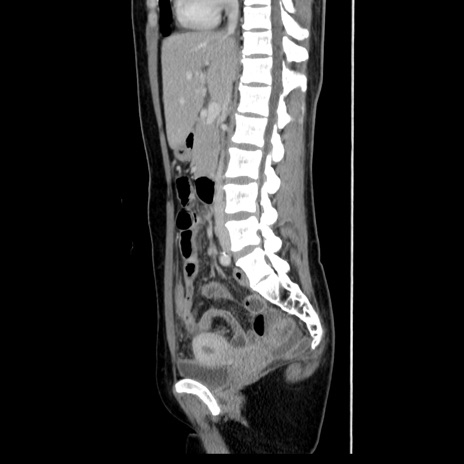

症例39(矢状断像)

【症例】40歳代女性

【主訴】上下腹部痛

【現病歴】2日目から下腹部痛あり。夜間は痛みで眠れなかった。昨日より上腹部痛と下痢が出現。臥位で痛みは軽快したため、休んでいた。本日になって臥位でも立位でも痛みが強くなってきたため救急要請。

【既往歴】子宮内膜症

【身体所見】部:平坦・軟、左上下腹部に圧痛あり、反跳痛あり。

【データ】WBC 21800、CRP 26.78

CT